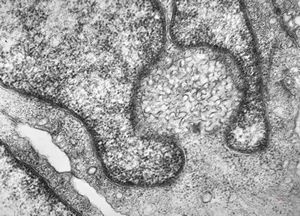

M, 11y. | mycosis fungoides v.s. - cerebriform nucleus of Sézary cell

F, 57y. | mycosis fungoides … cerebriform nucleus of Sézary cell

F, 37y. | mycosis fungoides … cerebriform nucleus of Sézary cell

M, 70y. | mycosis fungoides - Sézary cell

M, 70y. | mycosis fungoides - Sézary cell